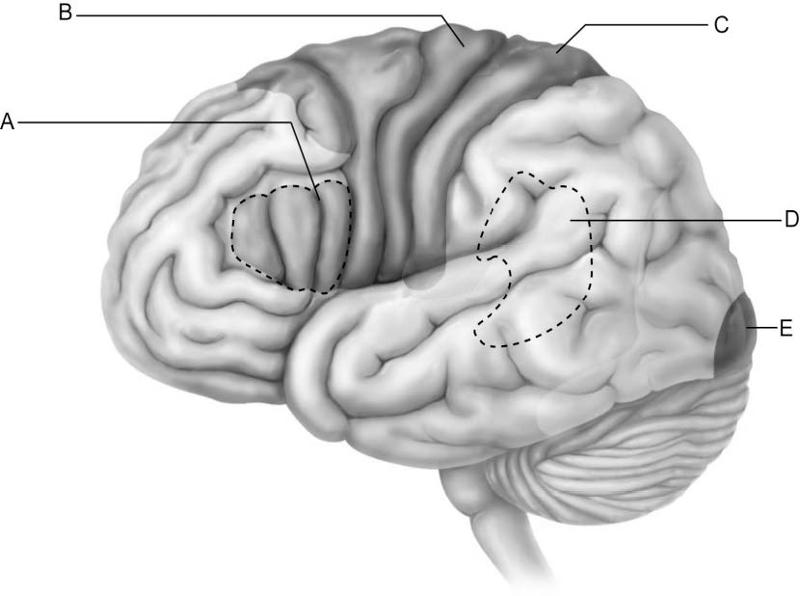

Which letter indicates the primary visual cortex, which receives

information from neurons in

the retina of the eye?

A)

A

B) B

C) C

D) D

E) E

E

Which letter indicates Broca's area, which controls the motor

movements necessary for

speaking?

A) A

B) B

C)

C

D) D

E) E

A

Which letter indicates Wernicke's area, which is important for

understanding spoken words?

A) A

B) B

C) C

D)

D

E) E

D

Which letter indicates an area that is characterized by huge neurons

known as pyramidal cells?

A) A

B) B

C) C

D)

D

E) E

B

Which letter indicates the primary somatosensory cortex?

A)

A

B) B

C) C

D) D

E) E

C